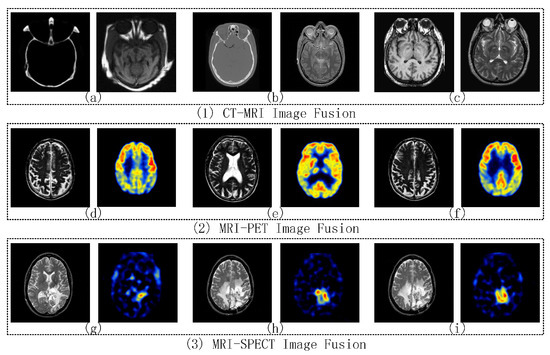

4.2.1. CT-MRI Image Fusion Comparative Experiments

4.2.2. MRI-PET Image Fusion Comparative Experiments

4.2.3. MRI-SPECT Image Fusion Comparative Experiments